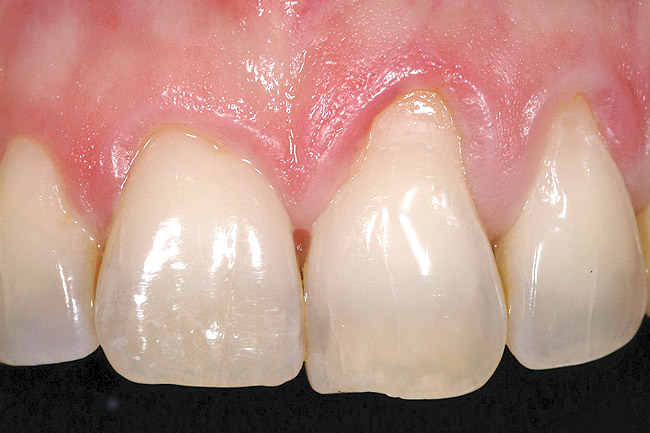

A 54-year-old non-smoking woman presented for correction of deep-wide gingival recession in the maxillary anterior (Figure 1 through Figure 3). The patient’s desires were to correct the gingival recession, balance the heights of contour of the tissues, and possibly undergo esthetic enhancement of the maxillary anterior with veneer restorations.

Figure 1  Case One Pretreatment clinical view, Case 1, maxillary right.

Figure 1

Figure 2  Case One Pretreatment clinical view, Case 1, maxillary anterior.

Figure 2